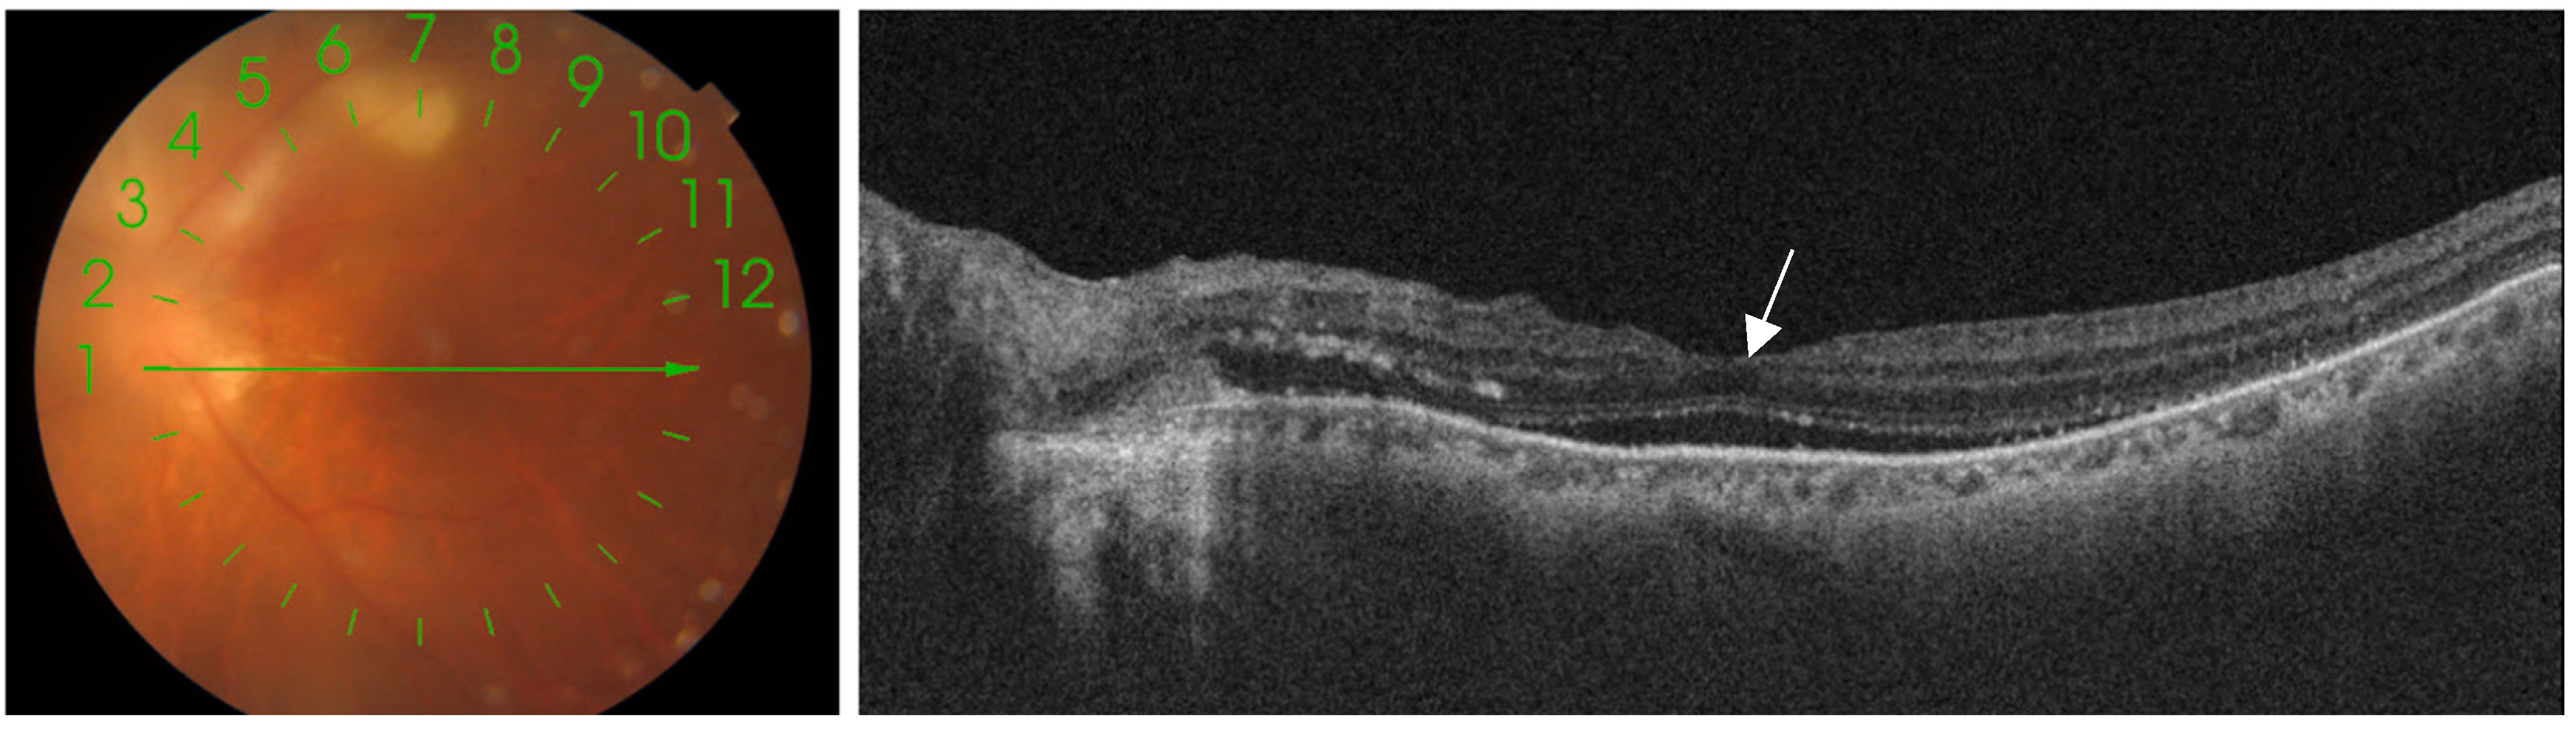

4.1. Multimodal Imaging Techniques

| Active Lesion | Gray-white necrotic foci in posterior pole with fuzzy borders; surrounding inflammation and hemorrhage | Subtle hyper/isoautofluorescence; thickening and detachment of posterior hyaloid over the lesion with irregular hyperreflective deposits | Early hypofluorescence, late progressive leakage at lesion margins; possible optic nerve head hyperfluorescence, vessel leakage, and vascular sheathing | Hypofluorescence; multiple satellite dark dots extending beyond the active retinal lesion; localized choroidal hypoperfusion | Increased intraretinal reflectivity with disorganization of neuroretinal layer boundaries corresponding to the area of retinitis; thickened and hyporeflective choroid beneath the active lesion; posterior hyaloid thickening with irregular hyperreflective deposits over the lesion | Hyporeflectivity of the lesion with diffuse choroidal dilation and many collateral vascular branches surrounding; decreased flow in outer retina and choriocapillaris | Fuzzy lesion margins, surrounding retinal edema; “headlight in the fog” appearance due to vitritis; ICGA shows multiple satellite dark dots |

| Inactive/Scar Lesion | Well-defined pigmented scar with sharp margins, often with central atrophy | Hypoautofluorescent | Early hypofluorescence due to pigment blockage or window defect, late staining at margins | Hypofluorescence; disappearance of satellite dark dots | Disorganized retinal layer reflectivity beneath a thin, hyperreflective choroid; RPE-choroid complex atrophy; persistent “hourglass configuration” with RPE changes and retina-RPE approximation | Marked reduction or absence of flow signal in all layers within the affected area | Clear boundaries, no signs of active inflammation; OCT shows tissue atrophy and “hourglass configuration” |

| Recurrent Lesion | New active lesion typically adjacent to old inactive pigmented scar (satellite lesion) | Mixture of hyper/isoautofluorescence (new lesion) and hypoautofluorescence (old scar) | Early hypofluorescence in new lesion area, late hyperfluorescence with leakage | Hypofluorescence; reappearance of satellite dark dots around new lesion | New area of retinal thickening adjacent to old atrophic area; posterior hyaloid thickening and epiretinal membrane formation | Changes in flow signal in new lesion area: increased in inner retina, decreased in outer retina and choriocapillaris | Coexistence of new active lesion and old scar; OCT shows both acute and chronic changes |